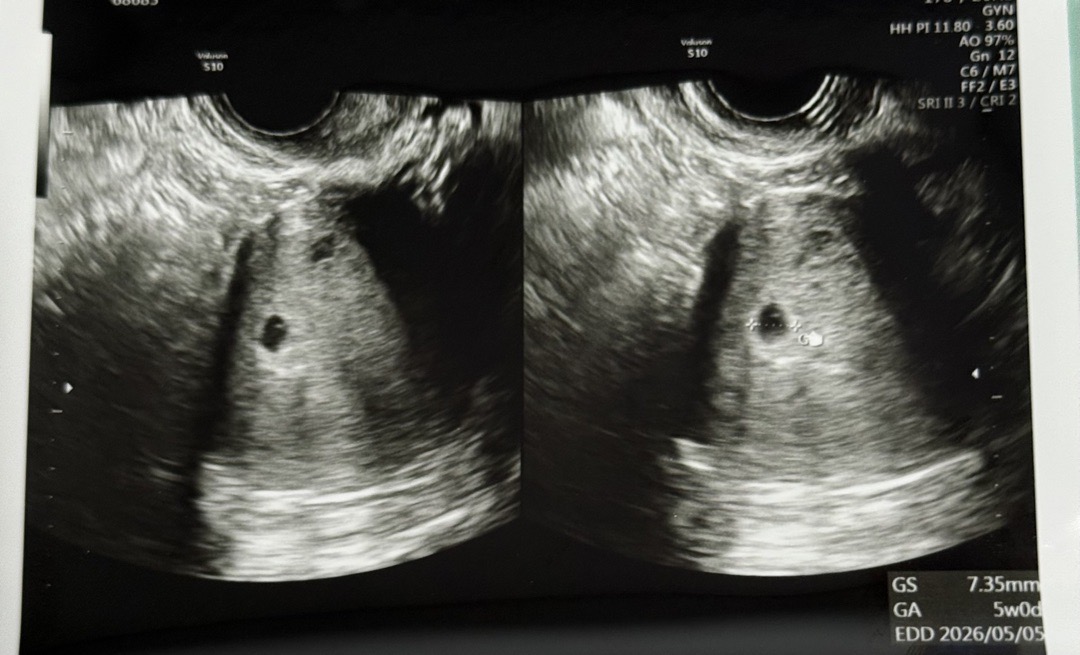

5주차에 병원 방문해서 초음파 보았습니다. 피고임이 있냐고 물어봤는데 없다고 하셨는데 유산방지로 질정을 2주분 처방해주셨습니다. 혹시 유산방지 가능성이 보여서 처방해주신걸까요..?

참고로 저는 올리신 사진보다 피고임 범위가 좀더 컸던거같애요